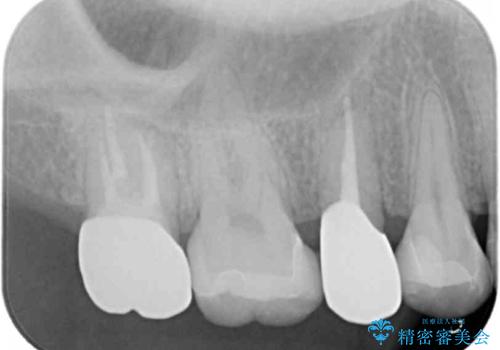

- 44万円 (セラミックインレー×2 ジルコニアクラウン×2)費用は治療当時の料金となります

症状に応じて適切な処置を行ったことで、抜歯を回避し良好な結果を得ることができました。